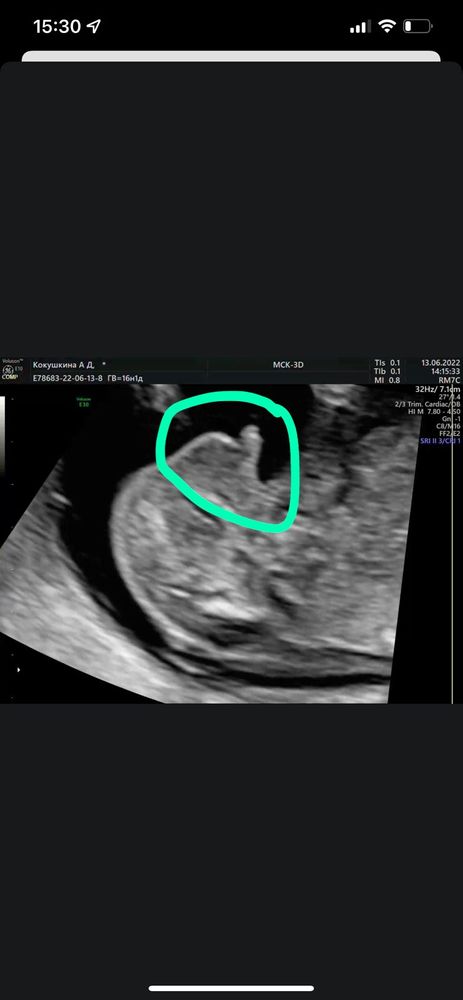

Определение пола 16 недель 🙏🏻

Девочки , подскажите пожалуйста кто вам кажется на фото. 🙏🏻16 недель 💫

Мне кажется то, что можно впринципе принять за половой бугорок, на деле кость, так как хорошо просвечиваются другие кости - лица, позвоночник. Думаю полового бугорка на снимке поэтому нет. Если 16 недель - я бы смотрела с ракурса с попы.

Anastasi-z, спасибо) так у вас нет предположений даже на кого больше похоже? Узист в 16 недель ориентировалась по половому бугорку🤔Сказала на 60% скорее всего девочка , угла наклона нет. А смотрю информацию , что в 16 недель уже по углу наклона не ориентируются...